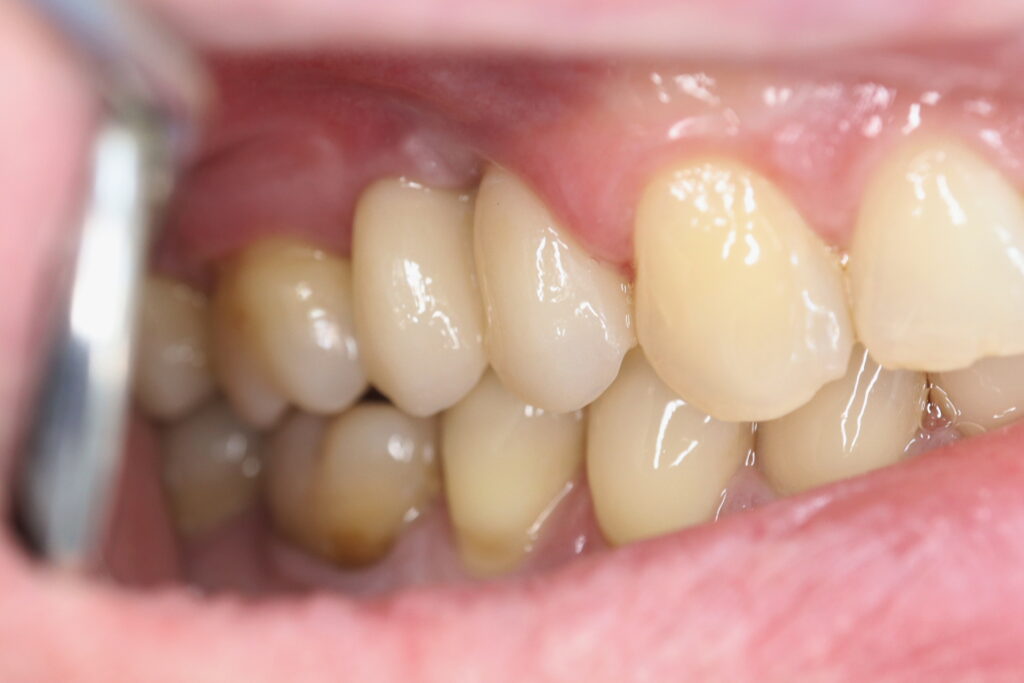

Результат

Пациенту были установлены 6 имплантатов Megagen AnyOne по системе All-on-6 на верхней челюсти и 4 имплантата на нижней по классической двухэтапной методике.

Спустя 27 дней был зафиксирован протез с опопрой на дентальные имплантаты из диоксида циркония с каркасом из титана.

Также на нижнюю челюсть был изготовлен мостовидный протез из 4х коронок (цирконий) с опорой на 3 индивидуальных абатмента с одной стороны и 1 коронка на иплантат с другой.